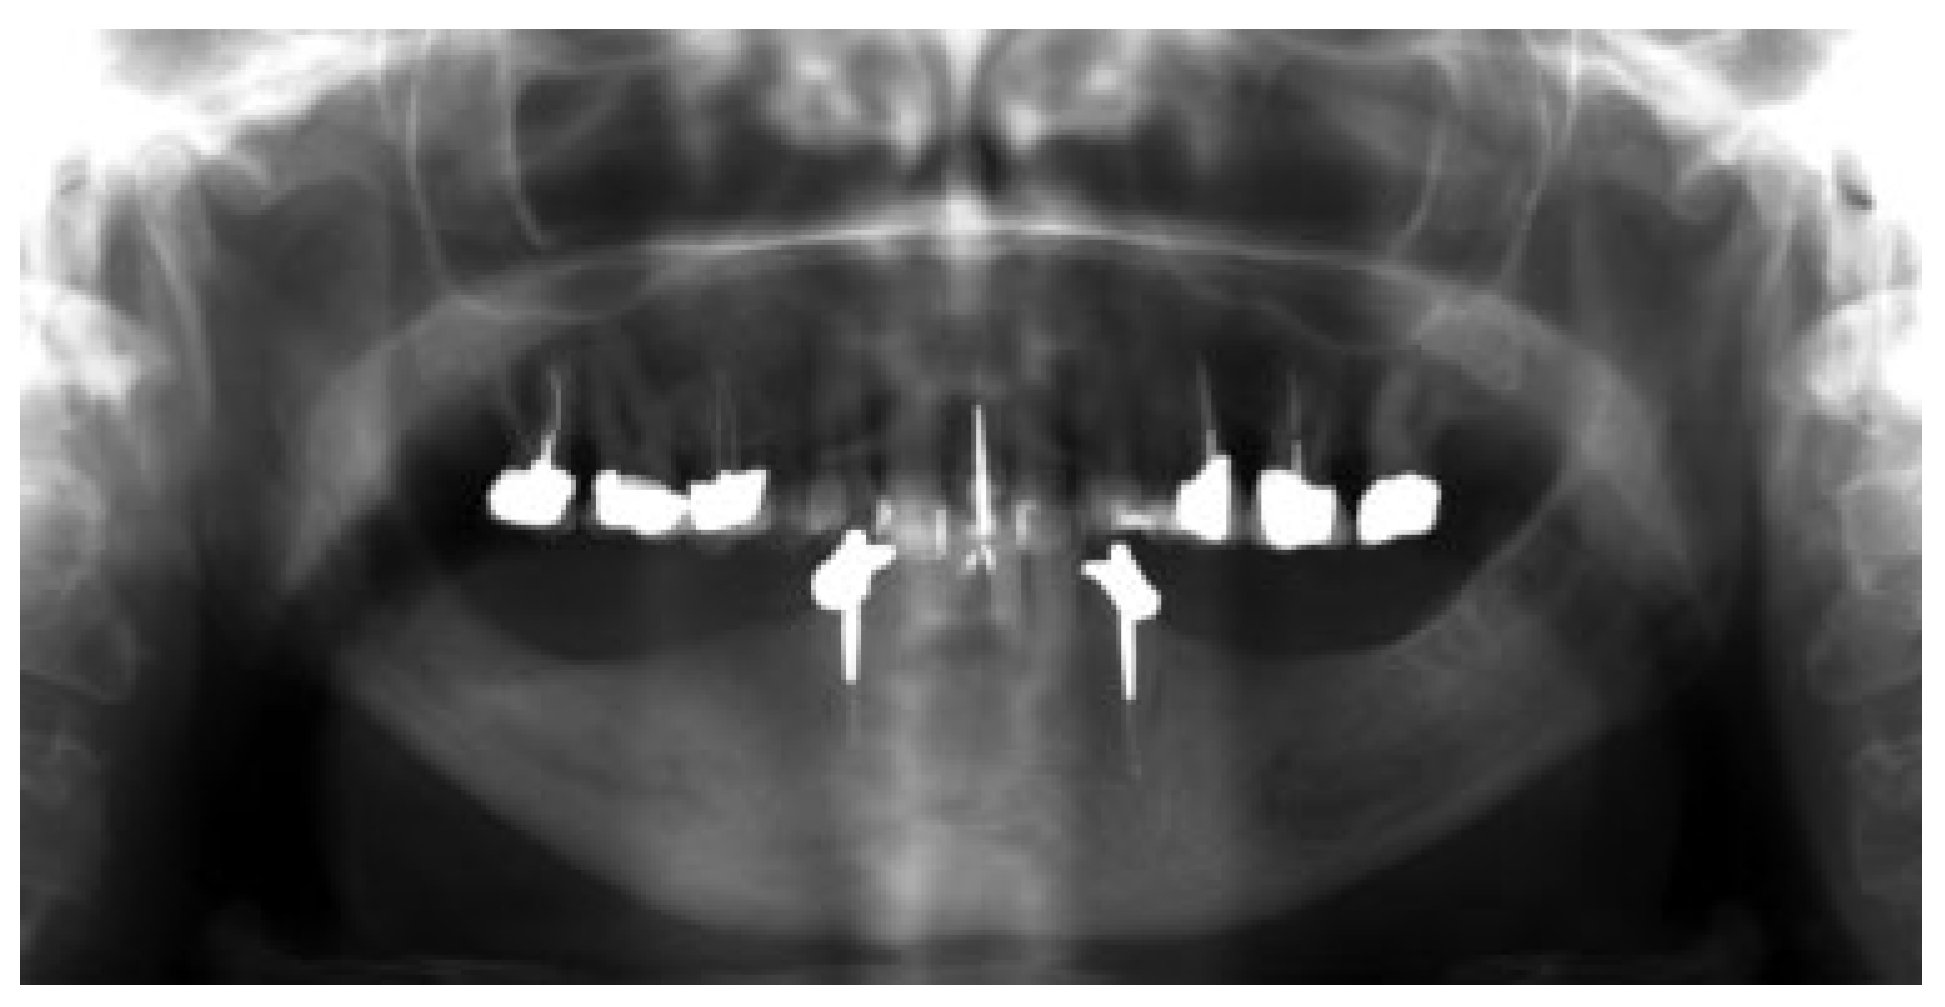

In 15 patients, 14 ablative surgical interventions were recorded, with 14 receiving primary or secondary reconstructive procedures; in one patient, no reconstructive procedure was performed due to a compounding medical condition (Table 2). This patient was excluded from further analysis due to lack of reconstruction. Eight patients had primary head and neck cancer, but in only four patients the condyle was involved due to infiltration, while four suffered from ORN. One patient suffered from a rare benign tenosynovial giant cell tumor. Two patients suffered from extensive osteomyelitis, and bisphosphonate osteonecrosis afflicted two patients. One patient had to be operated on twice due to hypertrophic bone formation around the metal condylar head and represents the only major complication in our series. She suffered facial nerve damage during the second surgery in a postradiated field, with the facial nerve lying on the reconstruction plate used in the first surgery (Figure 1). Six of the fourteen reconstruction surgeries took place in a radiated field, explaining the two plate exposures in an unrelated area, away from the condylar reconstruction. Two patients received total joint reconstructions combined with one and in the other two free flaps. Five patients received fibula flaps alone and one received a vascularized costochondral graft, while all of the others had metal condylar prostheses with or without a free flap (Figure 2, Figure 3 and Figure 4). Follow-up ranged from 2 to 84 months with an average of 30 months. In total, five patients suffered from complications that could be considered acceptable, as they all could be corrected with minor revision surgery or occlusal adjustment. One patient suffered from facial nerve damage after a reconstruction plate in which metal condyle had to be removed in a radiate. In 11 patients, reliable information was obtained regarding mouth opening of which 9 showed a marked improvement of more than 5 mm. Three patients had a decrease in mouth opening, but all could be regarded as functional as no mouth opening of less than 30 mm was recorded (Figure 4).

Figure 4.

Functional mouth opening 1 year after surgery.